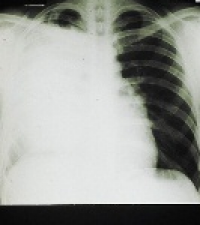

Up to now, early detection of COPD and associated lung damage, such as air trapping (air that cannot be exhaled due to overinflation of the alveoli) or pulmonary emphysema (holes in the lung filled with air that reduce the lung surface area) was not possible. Ankersmit and his team have now been able to show that protein HSP27 is a suitable marker in the blood for detecting existing lung damage—even in people who feel healthy and whose pulmonary function test results give no cause for concern.

Ninety-four apparently healthy male and female smokers (average age of 43) were studied by the University Department of Surgery, Radiology and Pulmonology at MedUni Vienna. The results of the study have been published in Respiration, the international journal of thoracic medicine. The test subjects voluntarily underwent a high-resolution CT scan. The results showed that 57.45% of test subjects exhibited signs of air trapping or air trapping AND emphysema, even though their pulmonary function test results were within the normal ranges. Moreover, the HSP27 value, which was determined using an ELISA kit from R&D Systems, showed a significant correlation with the lung pathologies detected by radiologists during the CT scan.